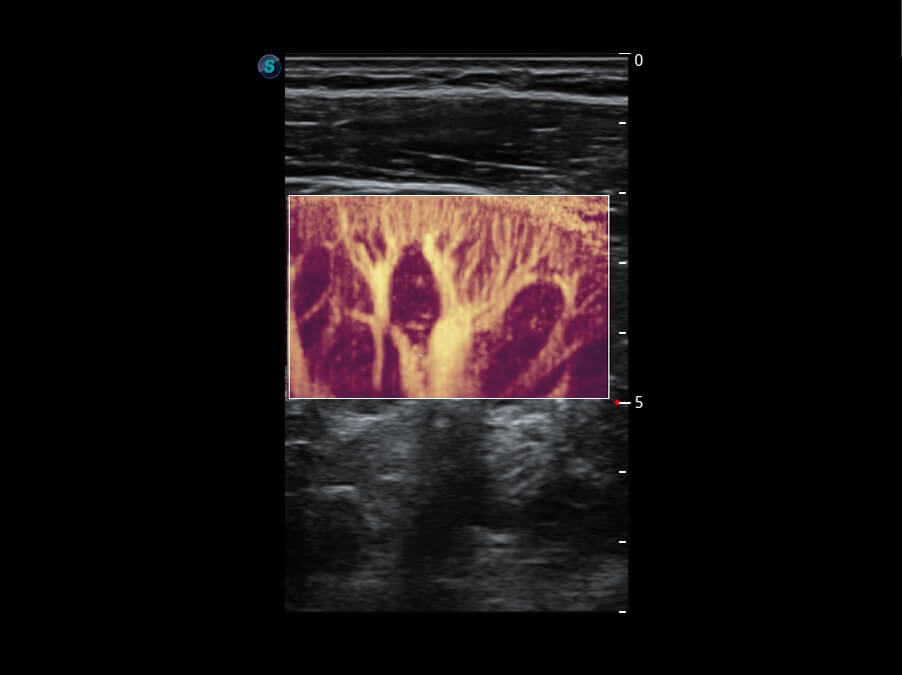

成像功能

性能优异的硬件架构,极大提升超声系统的运行效率和数据处理能力。相比以往超声成像系统,Wis+平台为您带来极快的响应速度和成像帧频,提升检查流畅度。

S60探头工艺,从前端信号处理每一个环节采集无损声学数据,真实还原组织原貌,再现解剖细节。